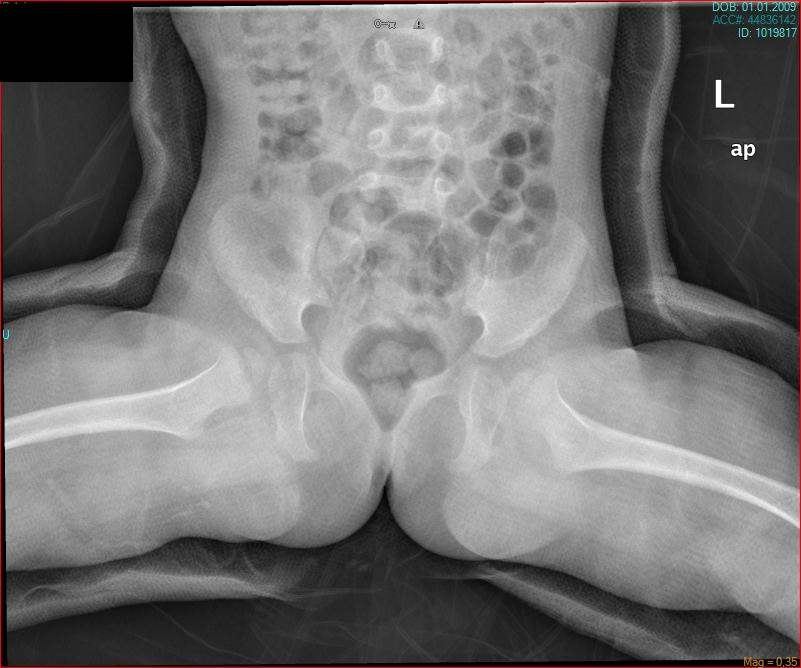

Congenital Pediatric Orthopedic DiseasesDec 30, 2021 | Case ExamplesBilateral GKD Case 1 Bilateral GKD Case 2 Bilateral GKD Case 3 Bilateral GKD Case 4 Congenital Clubfoot Fibuler Hemimeli Tibial Hemimeli PFFD